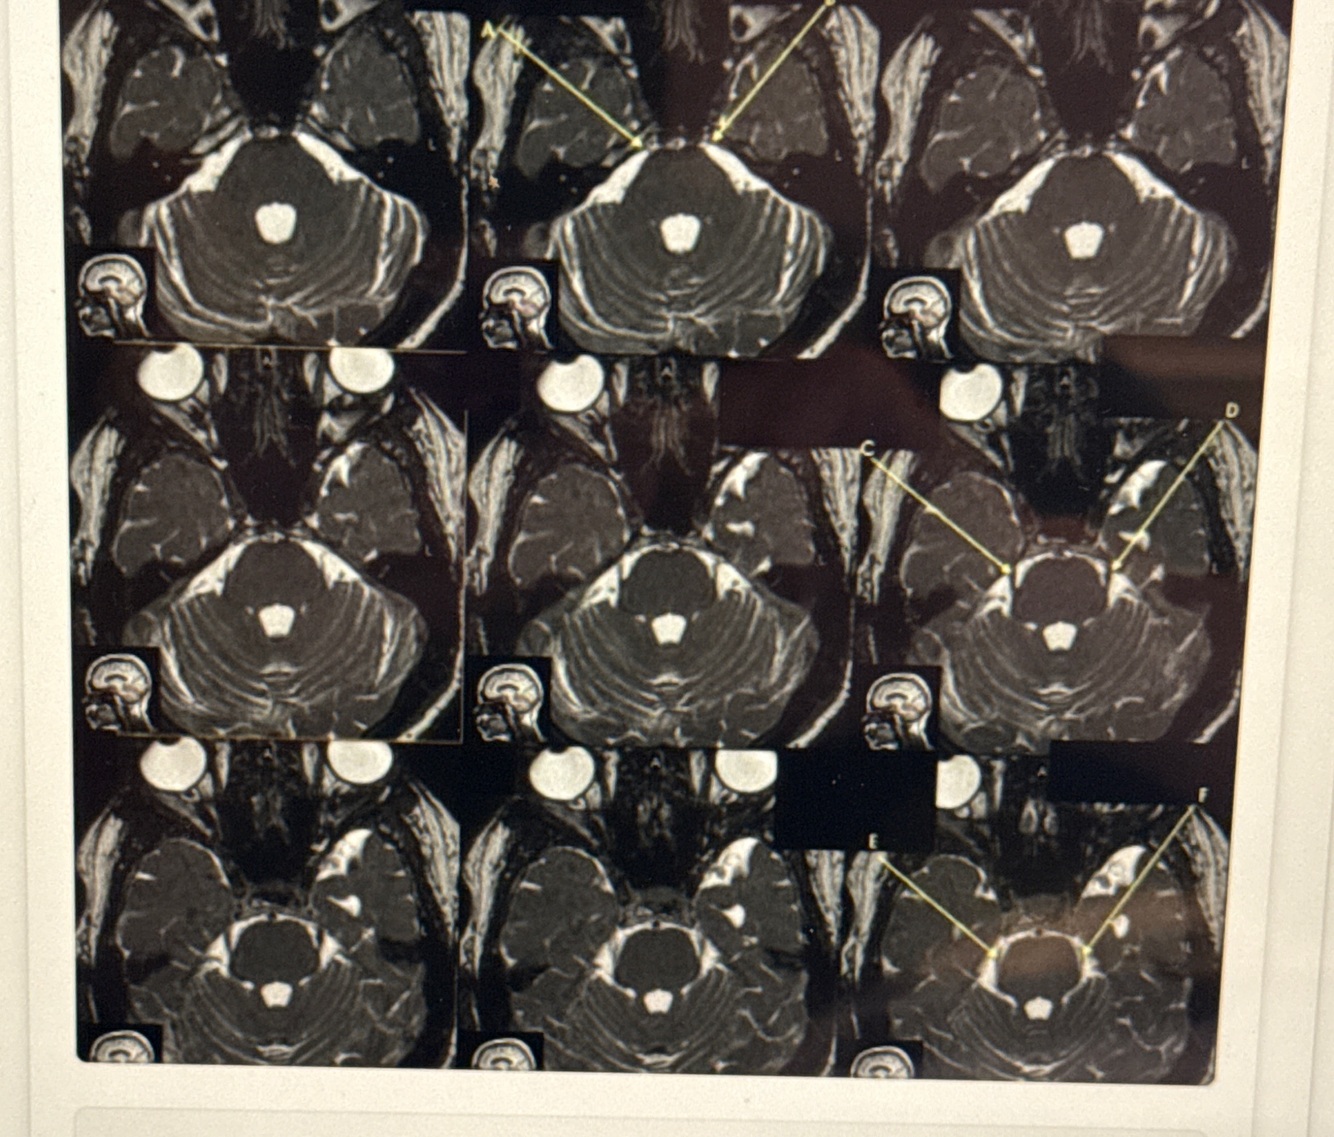

Cervical spine ideal scan plane is

-Visualized best in the Sagittal and Axial planes -Coronal Plane used to visualize and measure scoliosis

Cervical spine coverage which scan plane - • Cover from C2-3 to C7-T1 • Angled parallel with intervertebral discs

Axial

Which scan plane is this appropriate for when imaging cervical spine ? • Slices should cover all 7 vertebral bodies from right to left • Angled parallel to spinal cord

Sagittal